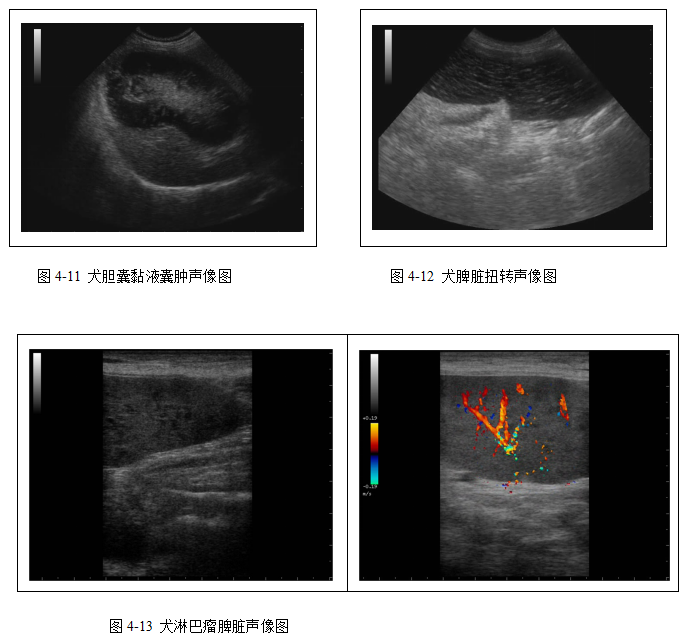

脾脏超声检查常对脾脏的尺寸、位置及回声实质是否异常进行评价。检查的适应症包括贫血或白细胞增多、X线检查脾脏明显增大、急腹症、急性外伤、腹部触诊脾脏肿块和未知原因的腹部疾病。影响脾脏的疾病通常会使脾脏增大,通过腹部触诊、X线检查或超声检查均可发现。超声检查最大的优点是其可以确定是否是局部的还是非局部的脾脏损伤,也可以鉴别损伤为腔性还是实质性,而且在有腹腔积液时超声检查会变得更有价值。在腹部创伤、脾扭转和脾脏动脉或静脉栓塞时,多普勒超声检查也会有很大帮助。

消化系统超声检查主要用于评估肝胆疾病(图4-7、4-8、4-9、4-10、4-11)和脾脏病变(4-12、4-13)。胰腺、胃肠道扫查在本教材中未涉及。